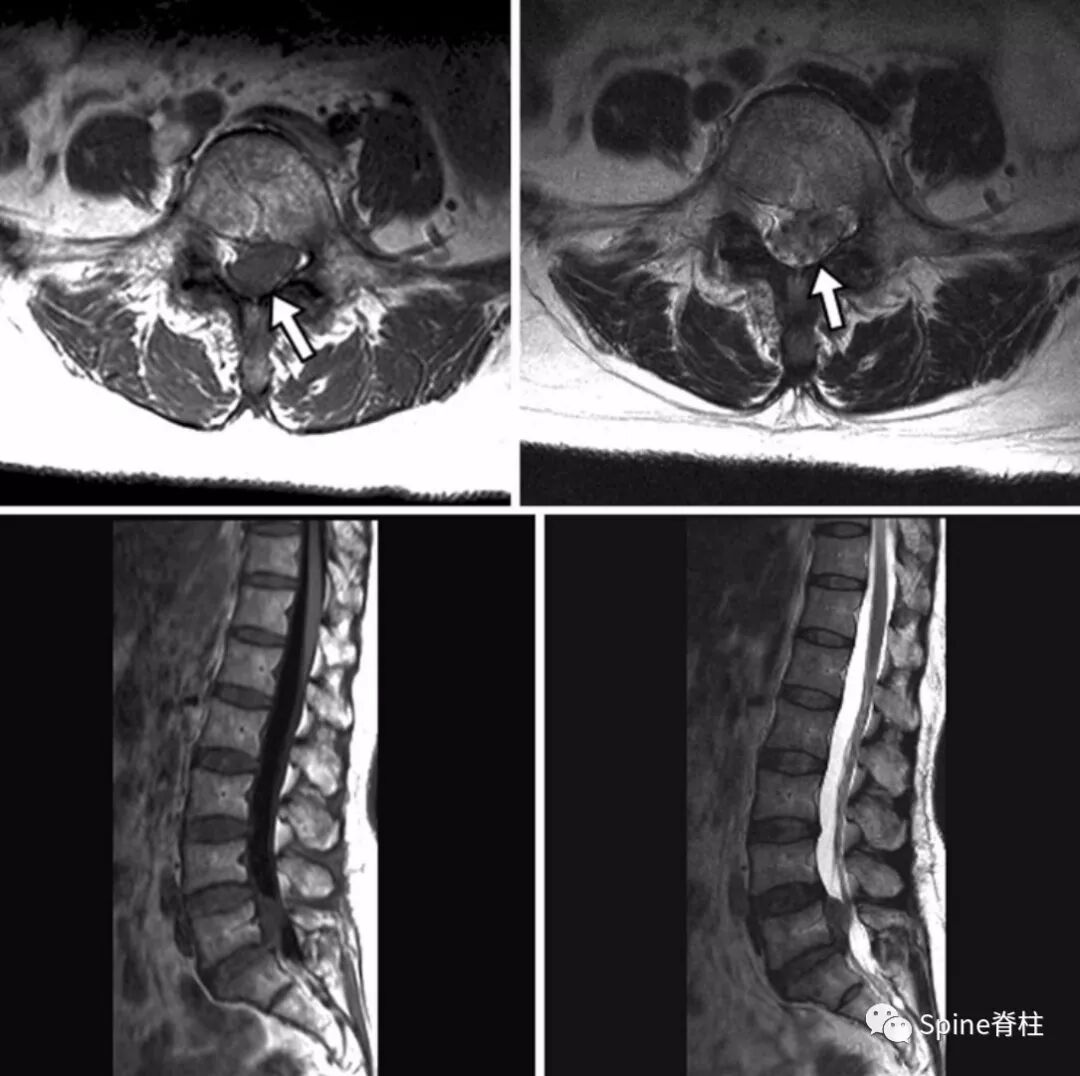

详解 硬膜内椎间盘突出症

详解 硬膜内椎间盘突出症 Spine脊柱 微信公众号文章阅读 Wemp